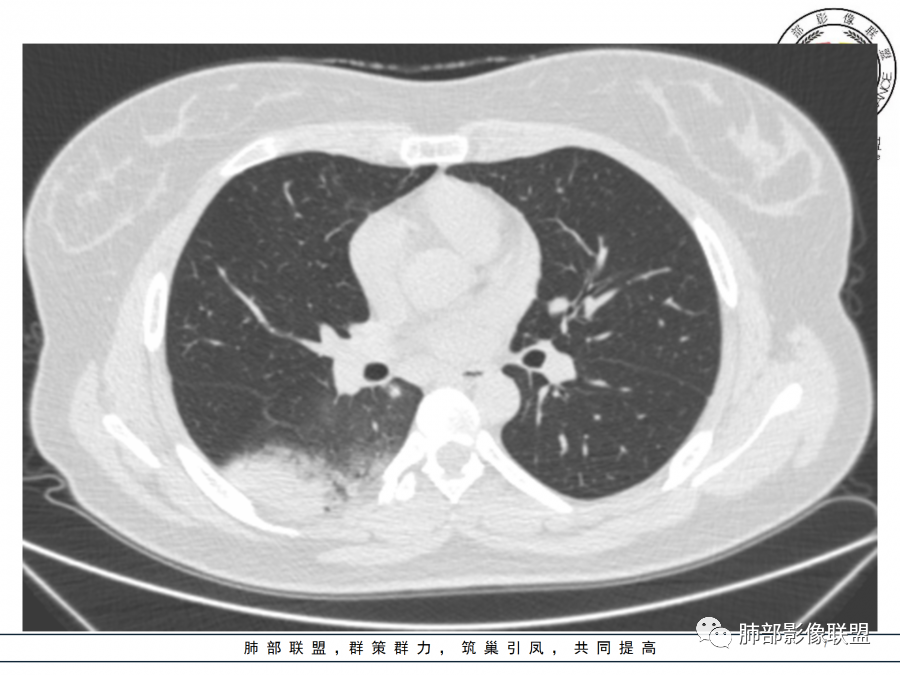

1.年轻女性,咳嗽、发热(38.8°),起病急,血象高。影像上大片实变影为主,一般会首先考虑细菌性肺炎,尤其是肺炎链球菌感染等。疗效不满意时考虑其他。

2.影像上怀疑其他病灶的理由有:

1)实变影为大小不等多中心性。

2)沿胸膜下分布趋势(不同于大叶性肺炎的肺叶“造型”)。

3)周围较大范围磨玻璃影及小叶间隔增厚。

4)病灶体积增大明显(叶间裂推移)。

3.腺病毒肺炎可以符合上述改变:实性密度,间质分布为主等。

4.隐球菌感染可以符合上述改变:胸膜下多中心实变密度为主,磨玻璃晕等。但隐球菌临床症状大多隐匿、迁延,影像变化缓慢。

5.本例患者血象高,影像渗出明显,尚不能排除混合感染可能。